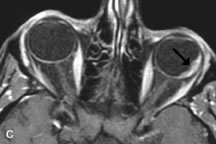

Fig. 18. A. T1-weighted, (B) T2-weighted fat-suppressed, and (C) T1-weighted fat-suppressed MR scans demonstrate a small dermoid cyst arising near the palpebral portion of the lacrinal gland (arrows). The lesion is similar in signal intensity to fat on the T1-weighted scan (A) consistent with a high adipose tissue content. The lesion shows fat-suppression and low signal intensity on the two fat-suppressed sequences (B and C) confirming its high lipid content.

Dermoid cysts appear as rounded, well-defined lesions typically contiguous with an orbital bony suture. The high-intensity signal on T1-weighted images is attributed to the sebaceous-produced lipid contents (Fig. 18).31,50 Mucoceles may demonstrate a hypointense or hyperintense signal on MR images, depending on the concentration of proteinaceous or inflammatory fluid components. The integrity of the bony walls of the expanded sinus cavities cannot be assessed on MR as well as by CT.37,50,55,56 A high-signal intensity on Tl- and T2-weighted images is characteristic of orbital chronic hematic cysts because of the blood-breakdown products within the cysts.57